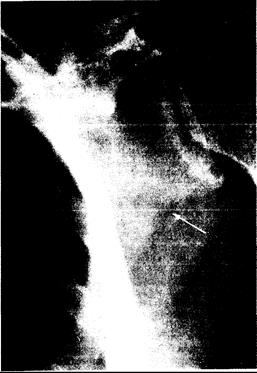

Рис. 337-3. Рентгенограмма лопатки 58-летней женщины с фосфатным диабетом.

Стрелка указывает на локализацию псевдоперелома, или зоны Лоозера.